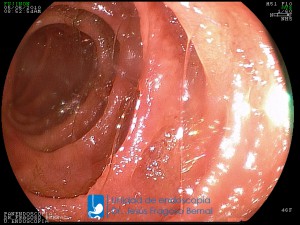

La Unidad de Endoscopía fue creada en 2002 por el Dr. Jesús Fragoso Bernal, es pionera en el estado por la utilización de la tecnología más avanzada, que nos permite ofrecer servicios integrales de diagnóstico y tratamiento para las enfermedades del aparato digestivo.

El profesionalismo de nuestro personal, altamente especializado, se distingue por la calidad y calidez de nuestros servicios con el objetivo de brindar una atención de excelencia en el ambiente más confortable para comodidad y seguridad de nuestros pacientes.

"La Unidad de Endoscopía se ha caracterizado por un progreso continuo desde su inicio marcando la pauta en los procedimientos endoscópicos en el estado de Tlaxcala y estando siempre a la vanguardia tecnológica."

Dr. Jesús Fragoso Bernal